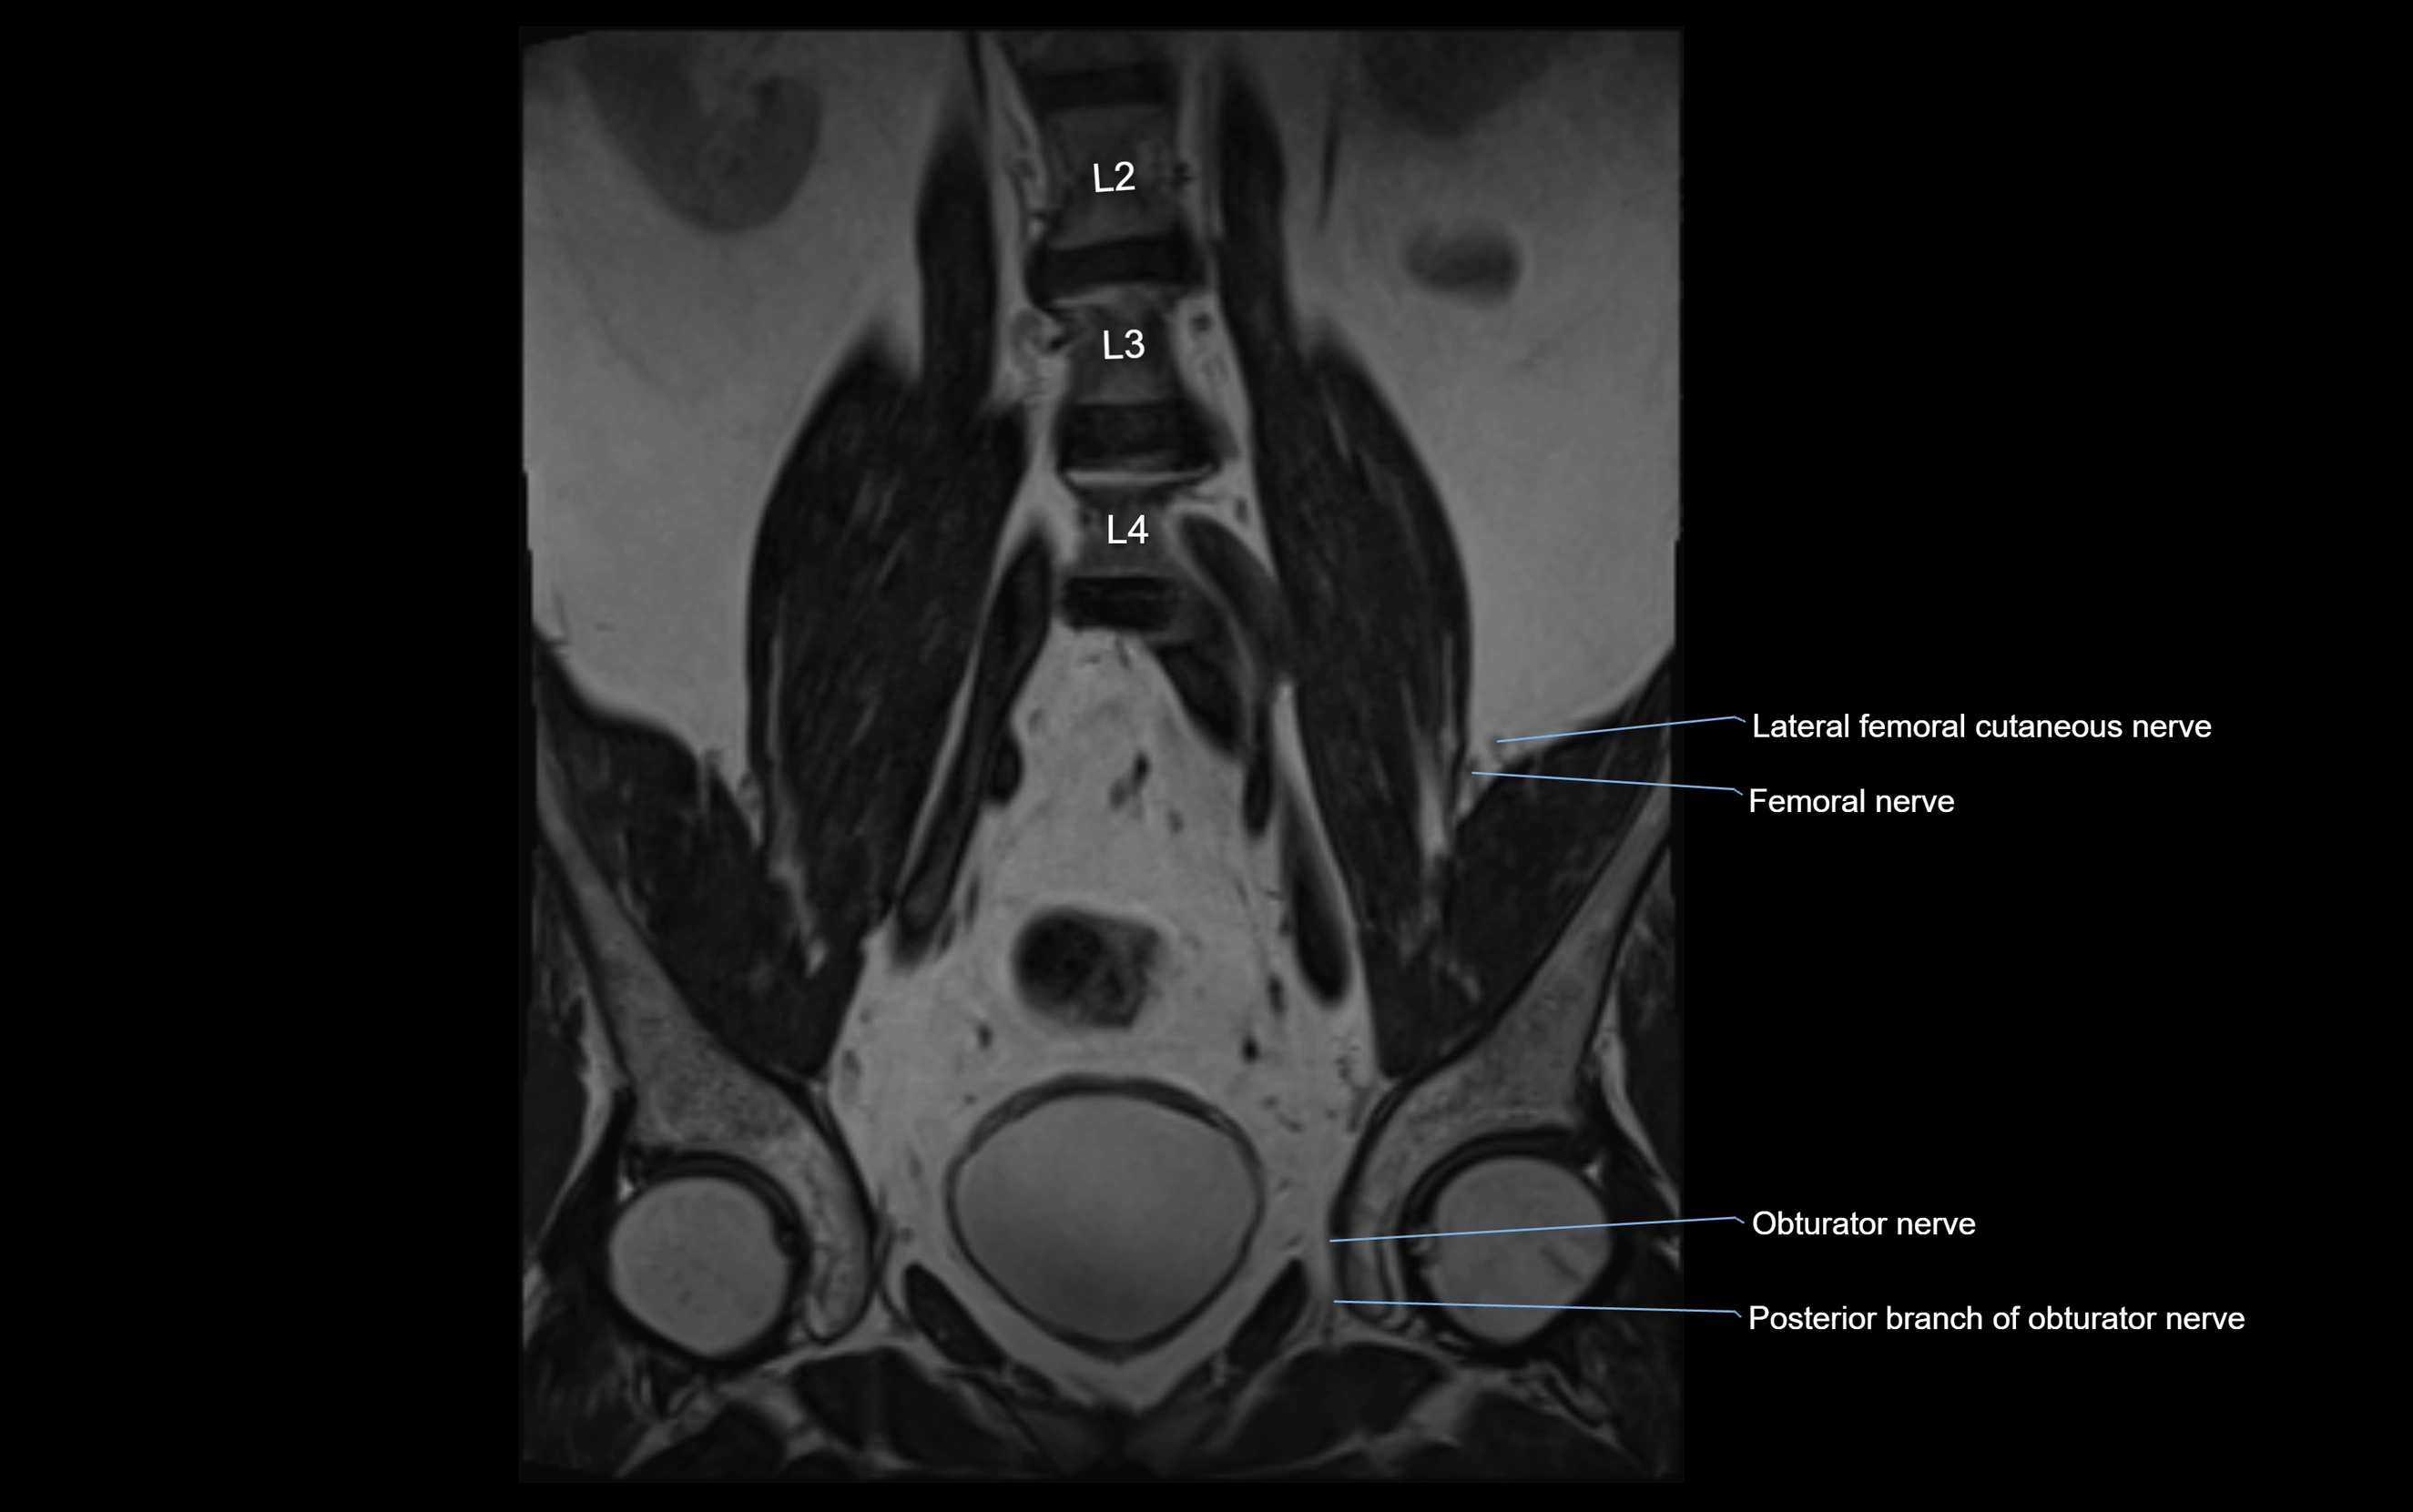

MRI Appearance

T1-weighted images:

• Nerve appears as a very thin low-to-intermediate signal intensity structure

• Surrounded by bright fat, aiding visualization

T2-weighted images:

• Nerve shows intermediate to mildly hyperintense signal compared to muscle

• Pathological involvement appears brighter

STIR (Short Tau Inversion Recovery):

• Normal nerve appears dark

• Inflamed or entrapped nerve appears bright hyperintense

T1 Fat-Sat Post-Contrast:

• Normal nerve enhances minimally

• Pathologic nerve (neuritis, entrapment, tumor infiltration) shows focal or diffuse enhancement

3D T2 SPACE / CISS:

• Nerve appears intermediate to mildly hyperintense compared to muscle

• Surrounded by bright fat or CSF, improving visualization

• Best sequence for mapping small pelvic nerves such as the anococcygeal